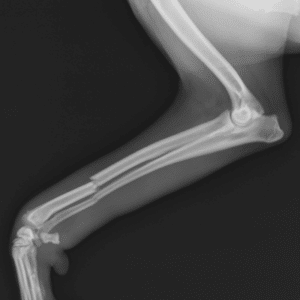

Image of an injured dog leg

Bone, Joint, and Cartilage Damage

When we talk about damage to bones, joints, and cartilage, we’re often dealing with more severe trauma or degenerative diseases. A fracture, for instance, results from a force that exceeds the bone’s strength, causing it to break. Joint dislocations and cartilage also damage disrupt the smooth movement of the joint, causing pain with every movement.